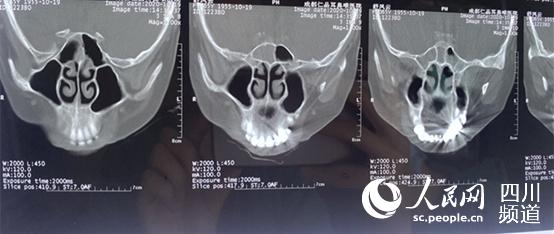

舒紅的鼻竇CT片。徐田莉 攝

本月中旬,舒紅來到成都仁品耳鼻喉?漆t院就診,經過系統檢查,診斷“慢性鼻竇炎、鼻中隔偏曲、過敏性鼻炎”。10月24日,舒紅接受了“鼻內鏡鼻竇開放術(藥物支架植入)+鼻中隔矯正術+鼻部高能聚焦超聲治療”。

成都仁品耳鼻喉?漆t院鼻科劉翠主任說:“術中發現舒紅患了慢性鼻竇炎中的霉菌性鼻竇炎,她之前的不適癥狀也是因為霉菌感染引起的,需通過手術,將鼻子中的霉菌團塊取出,舒紅才可一解鼻塞、頭痛之苦!